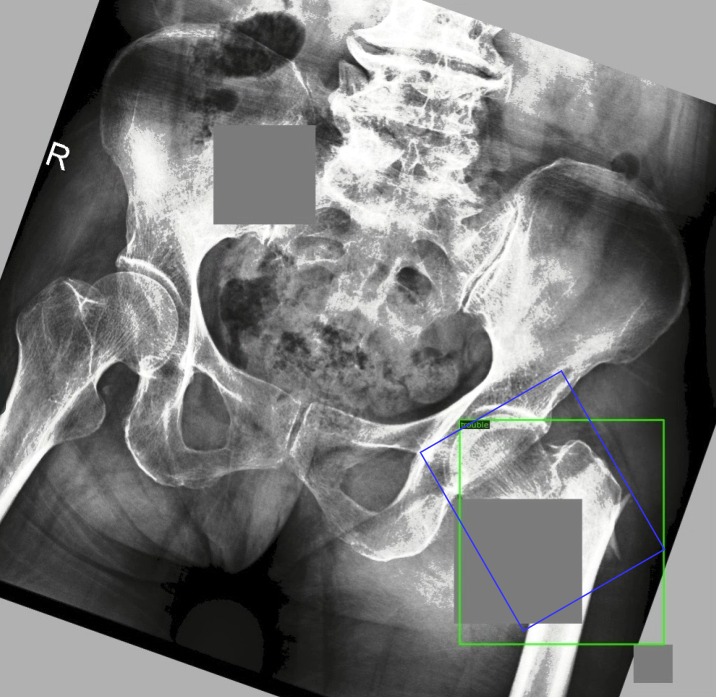

In this section, we compare our method with other state-of-the-art methods proposed in recent years. We first evaluate on Partial annotation data setting and compare our method with the results in STAC, Soft teacher and Unbiased teacher. Also the baseline of YOLOF and FasterRcnn is compared with our semi-supervised method in Table 2. We found that our method performed better than other methods in fracture detection. Specifically, the mAP of our method is 15.7%, 22.5% and 11.0% higher than the baseline on the 1%, 5% and 10% data sets, at the same time 2.4%, 0.2% and 2.3% higher than the previous methods. We evaluate the loss of model training and show the results in Figure 10. In order to compare the prediction results more intuitively, we visualized the baseline prediction using YOLOF and the prediction results of our semi-supervised framework in Figure 11.

Refer to caption

Figure 11: (a), (c) represent YOLOF baseline forecast results.(b), (d) represent prediction results of semi-supervised method (blue: annotation; red: detection results).